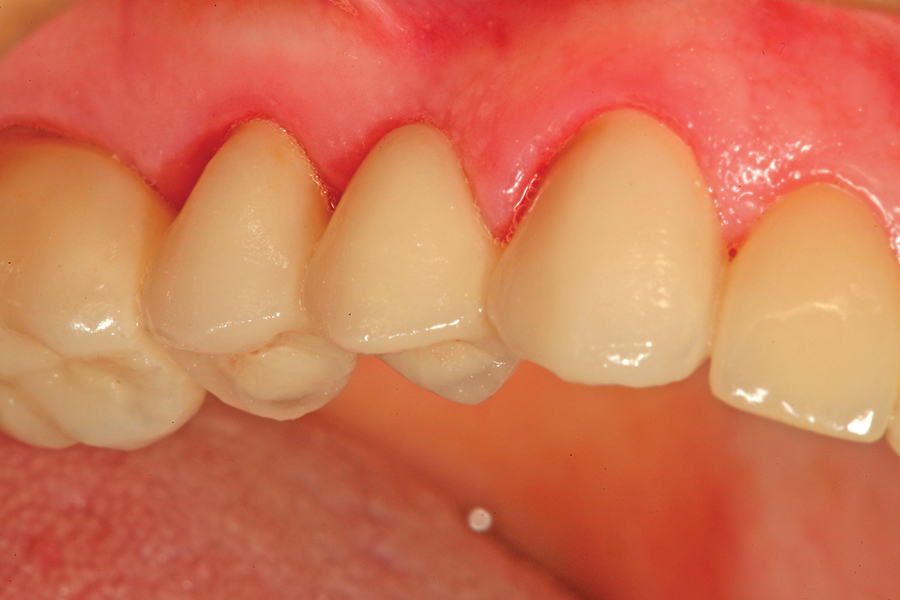

THE PERIMETER PREPARATION

The composite restoration is the basic foundation of the general dental practice. Countless composites are placed by dentists every day. Through the science of adhesive dentistry these restorations can be conservative and provide long term service. With time and function some breakdown may occur, usually at the margin of the restoration, the interface between tooth … Read more